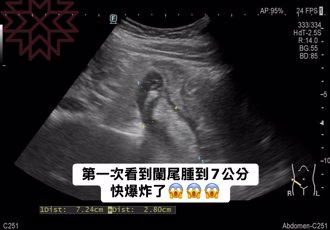

• 她胃超痛以為腸胃炎 醫一照驚:闌尾腫成7公分 快爆炸

她胃超痛以為腸胃炎 醫一照驚:闌尾腫成7公分 快爆炸

肝膽腸胃科醫師林相宏昨天分享,一名40歲女子胃超痛來看診,表示之前去掛急診抽血檢查說都正常,只是腸胃炎,但之後卻肚子痛到晚上睡不著,結果林相宏一照超音波嚇到,「天啊,我還第一次看到闌尾腫成7公分,快要爆裂」,難怪她痛成這樣。